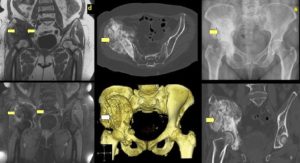

Мскт костей таза проводится с целью диагностики травм тазового кольца, опухолевых процессов, инородных тел в полости таза, патологии тазобедренных суставов, крестца и копчика. При необходимости тщательной оценки структур малого таза и мягких тканей рекомендуется использовать внутривенное контрастирование или прибегнуть к МРТ-исследованию.

Позволяет обнаруживать очаги уплотнения и разрежения, оценивать размеры, форму, расположение и распространенность патологических участков, выполнять трехмерную реконструкцию исследуемой зоны. Мскт костей таза проводится для уточнения характера повреждений при травмах таза (переломах, инородных телах).

Процедура используется для диагностики (в том числе – определения степени прорастания окружающих тканей) доброкачественных, первичных злокачественных и метастатических неоплазий. В некоторых случаях методика показана при аномалиях развития и воспалительных процессах.

Главное отличие процедуры от привычного рентгена — сканирование органических текстур человека в трехмерном изображении. Врач выстраивает 3D модель нужного участка организма. Шаг срезов не превышает одного-двух миллиметров, в зависимости от типа применяемого томографа. Высокая точность обеспечивает определение патологии даже при небольшом отклонении от стандартов.

МСКТ всех костей таза осуществляется без наркоза. Возможность получения сверхтонкого среза на аппарате последнего типа обеспечивает выявление недуга на ранних стадиях, что важно при диагностировании опухолевых процессов. Создание трехмерной модели костей таза помогает обнаружить все изменения и составить дальнейший план и прогнозы лечения.

МСКТ суставов и лучевых костей таза в большей степени дает качественное исследование костного аппарата и сочленений. В меньшей мере визуализируются рыхлые участки. На снимке томографии (Кт костей таза) обнаруживаются: